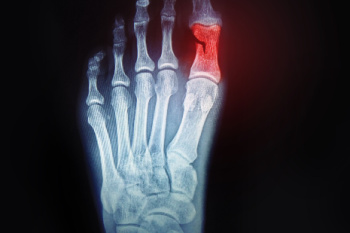

Facts About Broken Toes

A broken toe, or toe fracture, occurs when one of the bones in the toe is cracked or shattered due to trauma or excessive stress. Common causes include stubbing the toe, dropping heavy objects on it, or repetitive pressure from ill-fitting shoes. Symptoms typically involve pain, swelling, bruising, and difficulty moving the toe. In some cases, the toe may appear deformed or misaligned. For mild relief, it is vital to rest the injured foot and avoid putting weight on it. Pain may be managed by taking mild pain relievers. Keeping the toe elevated and using a buddy tape technique, where the injured toe is taped to an adjacent toe for support, can also assist in recovery. If you have broken your toe, it is suggested that you promptly schedule an appointment with a podiatrist who can make an accurate diagnosis and provide treatment.

What to Know About a Broken Toe

Although most people try to avoid foot trauma such as banging, stubbing, or dropping heavy objects on their feet, the unfortunate fact is that it is a common occurrence. Given the fact that toes are positioned in front of the feet, they typically sustain the brunt of such trauma. When trauma occurs to a toe, the result can be a painful break (fracture).

Symptoms of a Broken Toe

- Throbbing pain

- Swelling

- Bruising on the skin and toenail

- The inability to move the toe

- Toe appears crooked or disfigured

- Tingling or numbness in the toe

Generally, it is best to stay off of the injured toe with the affected foot elevated.

Severe toe fractures may be treated with a splint, cast, and in some cases, minor surgery. Due to its position and the pressure it endures with daily activity, future complications can occur if the big toe is not properly treated.